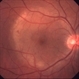

Syphilis Placoid Epitheliopathy

50-year-old patient, syphilis placoid epitheliopathy.